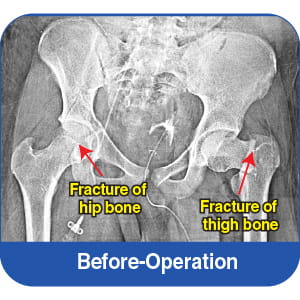

Fractures in the hip and pelvic bones

Reconstruction of the fractured hip bone

The hip fracture required meticulous reconstruction to restore joint stability and mobility.

Fracture fixation of the hip joint

Advanced orthopaedic implants and fixation techniques were used to align and stabilise the bones.